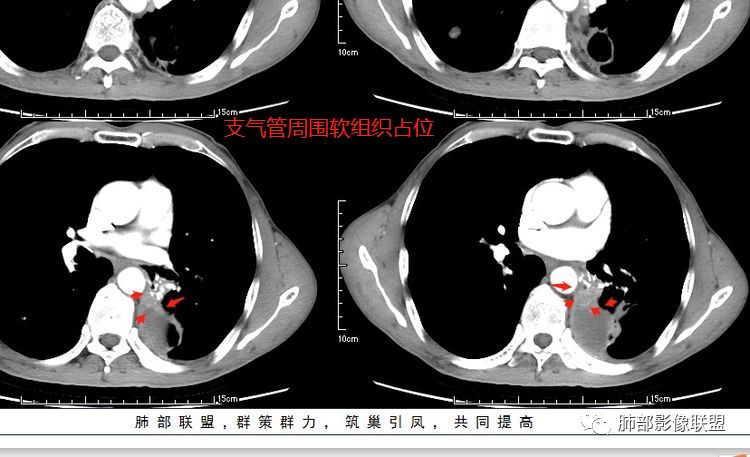

患者老年男性,咳嗽、咳痰、痰中带血伴胸闷2月余。长期大量吸烟史。查肝肾功能、血糖、血脂、心肌酶、电解质、血沉、C反应蛋白、抗“O”、类风湿因子、抗核抗体谱无明显异常。肿瘤标志物提示NSE、CYFRA21-1稍升高。胸部CT:肺气肿背景,左肺下叶后基底段不规则肿块影,见支气管截断,内见大片状低密度区及部分血管影,增强轻度强化,远端空洞形成。双肺多发不规则实性结节影、见毛刺、胸膜牵拉及血管集束,结节内见空洞形成,部分可见血管影,多位于胸膜下。双肺见多发肺大泡。综合考虑左下肺恶性病变并双肺转移。鳞癌或淋巴瘤可能。鉴别血管炎性病变及真菌感染。

张延军:双肺多发结节,空洞影,后者洞壁厚薄不均匀,部分腔内丝丝落落,呈分叶征,边缘见毛刺影,病灶大部分位于胸膜下,与血管相连,右肺下叶前基底段结节近段支气管截断,远端见空腔。左肺下叶病灶密度不均,背段支气管壁增厚,管腔狭窄。考虑1.双肺下叶占位性病变伴肺内空洞性转移 2.多原发的占位 3.肉芽肿性血管炎代排。

无发热,其他慢性细菌先不考虑,有的低毒的,但是结节形态还是比较不规则的,分布也是比较随机,更像原发病灶。真菌方面,结节没有融合,坏死也是液化坏死,不符合隐球菌,曲霉不符合IPA,慢性吸入的也少见。结核没有树丫,不考虑。鉴别主要是GPA,和肺癌。GPA不支持点是皮肤,肾脏没有累及,ANCA不支持。。。肺癌主要是腺癌和鳞癌转移。比较支持的是淋巴结肿大,和左下肺的主病灶,支气管堵塞和异常强化。还有分叶,局部膨隆。可以建议支气管镜检测。

本病例左肺下叶肿块,有深分叶、毛刺、胸膜牵拉凹陷、支气管截断及纵隔内淋巴结肿大等征象,都均支持病灶为恶性,如腺癌,而且叶间裂的多发结节也提示是腺癌来源可能大;双肺多发结节、肿块,大部分病灶有分叶、毛刺及胸膜凹陷的恶性征象,与原发肿瘤本身的性质有关,所以应该与左肺下叶肿块同源,而且双肺多发病灶内空洞也具有多样性;